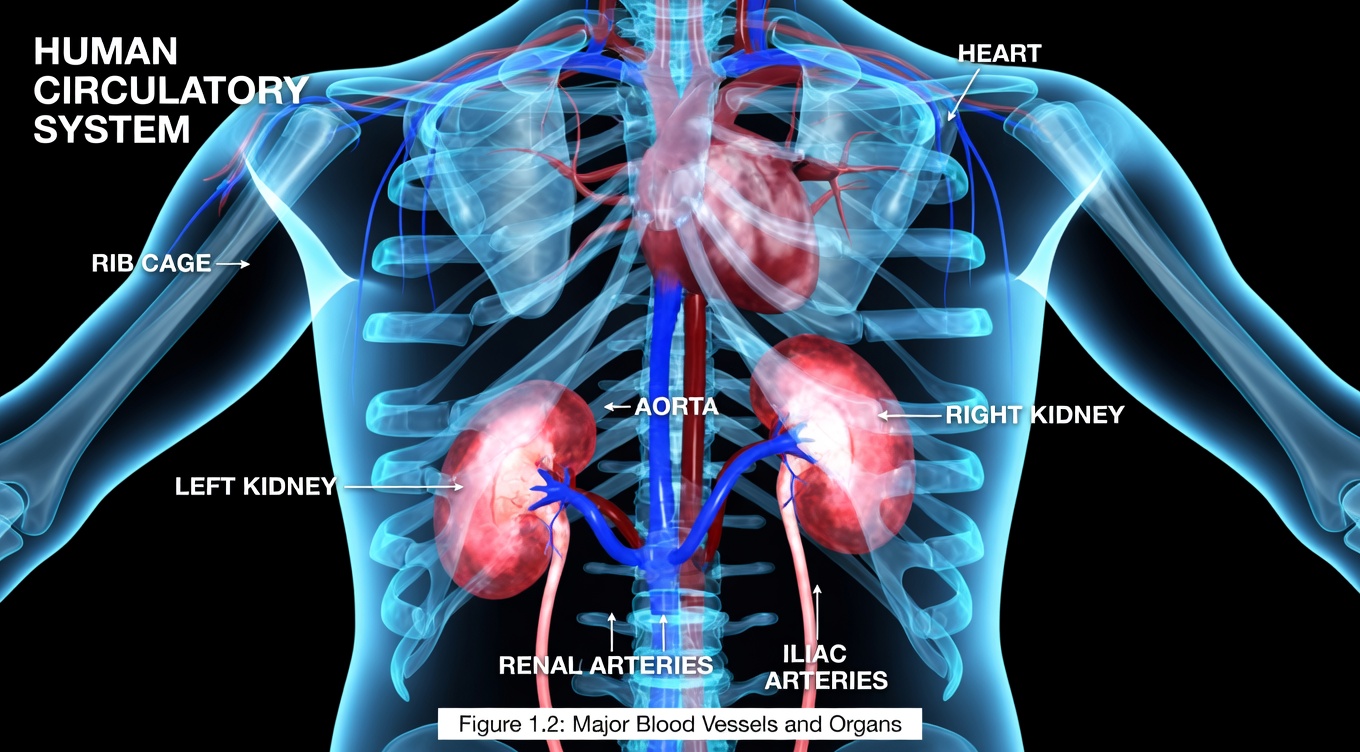

Why Kidney Health Deserves Your Attention

If ongoing fatigue and subtle discomfort linked to kidney strain have been wearing you down, a natural kidney support drink may be the low-effort evening habit you’ve been looking for. Modern diets loaded with salt, sugar, and processed ingredients can quietly place extra pressure on the kidneys, increasing concerns about long-term energy, comfort, and well-being.

Hydration plays a crucial role in kidney function, and choosing a soothing beverage at night is one way to align with this fundamental principle.

On a more personal level, when your kidneys are working overtime to filter waste and regulate fluids, you may notice more than just occasional tiredness—there can be a sense of heaviness, discomfort, or unease. A natural kidney support drink offers a simple, comforting practice that supports your body as it works overnight. Proper fluid intake helps maintain normal electrolyte balance, and a warm beverage can be a gentle complement to that process. If you often worry about how your lifestyle affects these vital organs, building this drink into your bedtime routine can bring a sense of proactive calm.